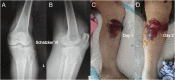

Background: Acute compartment syndrome (ACS) is an orthopedic emergency that commonly occurs after severe tibial plateau fracture. Fracture blisters form on the skin, and it was found in our previous study that when blisters form, the compartment pressure significantly decreases. However, the potential mechanism underlying this pressure decrease has not yet been elucidated. Methods: To obtain a comprehensive understanding of the changes that occur after blister formation on the skin, the changes in tight junction expression in the skin after tibial plateau fracture were observed. Blister samples and normal skin were collected from patients with bicondylar tibial plateau fractures with or without blisters. The epidermis thickness was measured, and the difference in the levels of K1, K5, K10, and skin barrier proteins such as claudin 1, claudin 2, and occludin between the two groups was evaluated by immunochemistry analysis, immunofluorescence, Western blotting, and qPCR. Results: The skin was thinner and the levels of K1, K5, and K10 were significantly decreased in blistered skin. Furthermore, the PI3K/AKT pathway was found to be activated, and the tight junction expression was significantly decreased in blistered skin. This indicates that the paracellular pathway, which is essential for accelerating fluid accumulation in blisters and indirectly decreases compartment pressure, was activated. Conclusion: Changes in the tight junction expression after blister formation may underlie blister fluid formation and indirectly explain the decrease in compartment pressure under blistered skin after severe tibial plateau fracture.